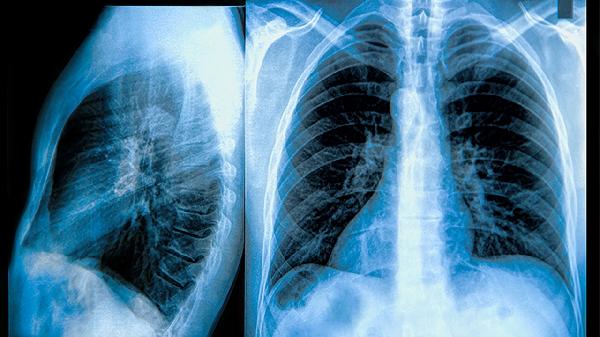

肺结节30毫米怎么了?

3、感染因素:例如,当真菌或结核分枝杆菌侵入肺部时,很容易引起肺部病变。此时,在进行影像学检查时,会发现肺部有阴影和结节样变化。